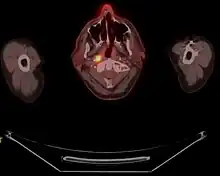

Staging

Staging of nasopharyngeal carcinoma is based on clinical and radiologic examination. Most patients present with Stage III or IV disease.

Stage I is a small tumor confined to nasopharynx.

Stage II is a tumor extending in the local area, or that with any evidence of limited neck (nodal) disease.

Stage III is a large tumor with or without neck disease, or a tumor with bilateral neck disease.

Stage IV is a large tumor involving intracranial or infratemporal regions, an extensive neck disease, and/or any distant metastasis. [16]